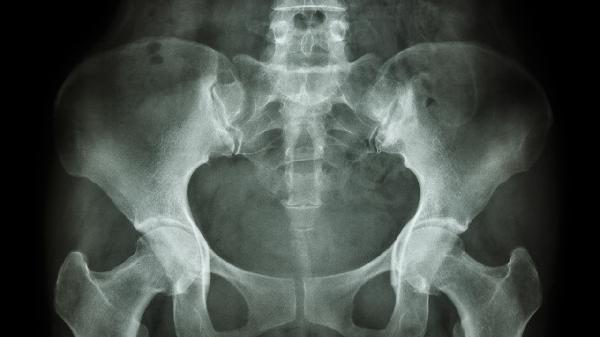

骨盆修复后需注意休息制动、避免负重、保持伤口清洁、定期复查、科学锻炼等事项。骨盆修复主要针对产后盆底肌松弛或骨盆骨折等情况,需根据具体修复方式调整护理方案。

骨折患者术后1个月需拍片查看骨痂生长情况,产后修复应每2周评估盆底肌张力。生物反馈治疗需按疗程完成,漏尿症状未改善者需调整电刺激参数。修复6个月后需进行骨盆CT三维重建评估稳定性。